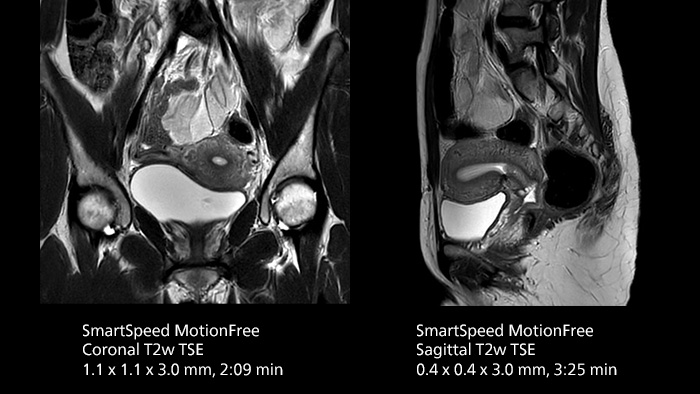

After using Philips SENSE, Mermaid Beach had adopted Compressed SENSE that offers a k-space sampling approach to speed scans while preserving details. “And now SmartSpeed enables denoising the sparse under-sampling in a new way that has allowed us to increase acceleration and bring image quality to a whole new level,” notes Kennedy, “It’s truly revolutionized our MRI work space, especially for difficult patients.”

Philips SmartSpeed has multiple approaches to denoising. Raw k-space data, coil sensitivity and coarse background information are all used and reconstructed with artificial intelligence (AI) to provide true resolution in shorter scan times1 with more sequences. Kennedy states, “I noticed that since the introduction of SmartSpeed, our day is a lot less stressed. When complicated exams need extra time, we just get on with them. And if we need to do something new or extra, we have the time for it and our workflow is still a lot more efficient.”

The broad applicability of SmartSpeed allowed the imaging center to use this technology across many scan types, including non-cartesian imaging as used for motion correction in uncooperative patients or challenging anatomies.